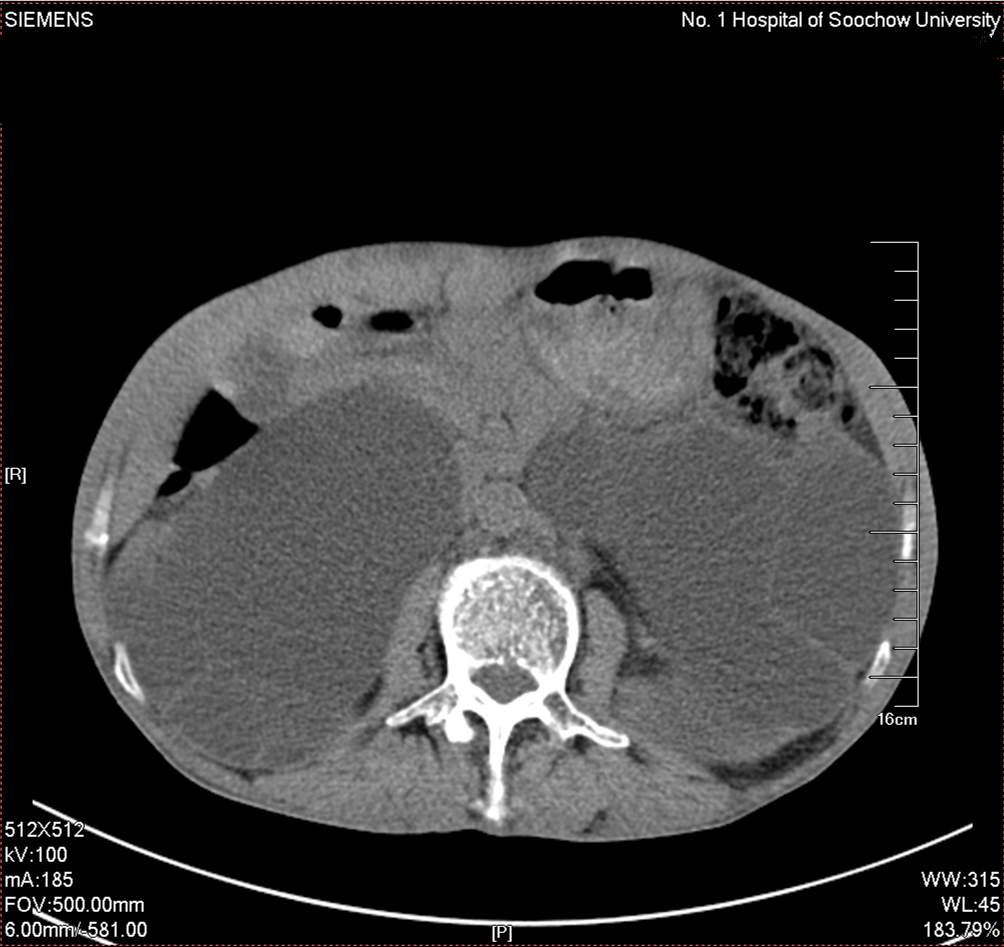

2016年02月手术患者,男性,47岁,河北人,农民,主诉双侧腰部酸胀一年余,伴尿少三天;五年前曾因输尿管结石在当地予以震波碎石3次,后疼痛缓解后未重视,五年来未予以复查,三天前出现尿少,腰部酸胀加重与当地医院就诊后发现病情危重遂来我院求诊,CT:双侧肾脏重度积水,皮质菲薄,双侧输尿管上段扩张明显,双侧输尿管中段结石,左侧结石约1.7cm,右侧约2.8cm左右,GFR:左侧11.7ml/min,右侧16.1ml/min。肾功能:Cr 516umol/L;术前诊断:双侧输尿管结石 双肾重度积水 肾功能失代偿;行双侧经皮肾穿刺造瘘术,保护肾功能,十天后Cr下降至236umol/L,方行双侧输尿管镜检,但由于输尿管梗阻时间太长,输尿管迂曲扩张明显,中段输尿管与周围脏器严重黏连,输尿管镜无法顺利上行,遂行双侧输尿管切开取石术+双侧输尿管裁剪成型术。

CT检查提示:双侧肾脏重度积水双侧输尿管中段结石 双侧输尿管上段积水扩张